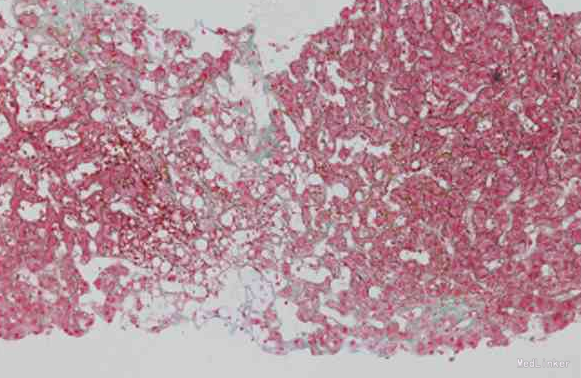

随访:未完成 讨论:该患者的血管彩超检查提示肝静脉纤细,血流减慢,但未见肝静脉或肝段下腔静脉狭窄、血栓,符合肝窦阻塞综合征的表现。 病理学检查提示肝组织淤血,肝窦高度扩张,尤其发现终末肝静脉内膜纤维性增厚、管腔狭窄,符合肝窦阻塞综合征的病理学特有表现。腹部CT检查提示3支肝静脉不显影,符合肝窦阻塞综合征的表现。 因此,结合血管超声检查、肝穿病理学检查及腹部增强CT检查结果,可排除巴德-基亚里综合征,确诊为肝窦阻塞综合征。 但肝窦阻塞综合征的常见病因是摄入吡咯双烷类生物碱(多存在于土三七中)或因器官移植后发生免疫排斥所致,这与该患者不符。 但是,该患者在6年前曾经接触过高浓度的二氧化硫,时间为半年,考虑其肝窦阻塞综合征的病因可能与此相关。因此,该患者的最终诊断为肝窦阻塞综合征。